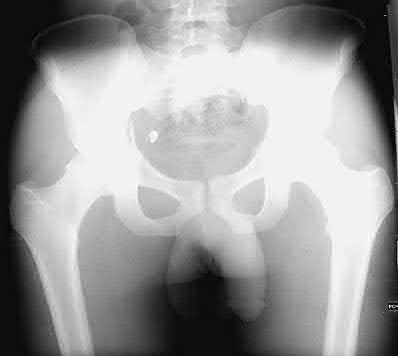

A 6-month-old female is evaluated for developmental dysplasia of the hip (DDH). Radiographs are obtained. Which radiographic line is drawn vertically downwards from the lateral edge of the acetabulum to assess hip subluxation?

Options:

Correct Answer: Perkin's line

Explanation:

Perkin's line is a vertical line drawn downward from the lateral margin of the acetabulum, perpendicular to Hilgenreiner's line (which is drawn horizontally through the triradiate cartilages). In a normal hip, the ossific nucleus of the femoral head should sit in the lower medial quadrant created by the intersection of these two lines.